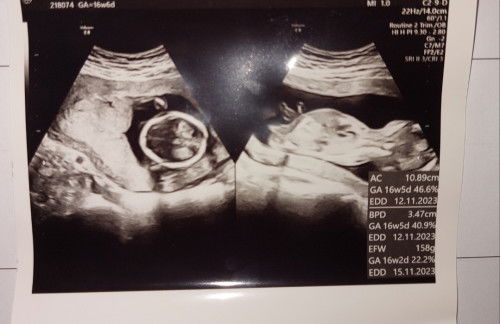

16w kayanya blm keliatan Bun, kalo udh keliatan pasti obgynnya ngasih tau soalnya aku jg JK nya baru keliatan pas usia kandungan 7 bulan